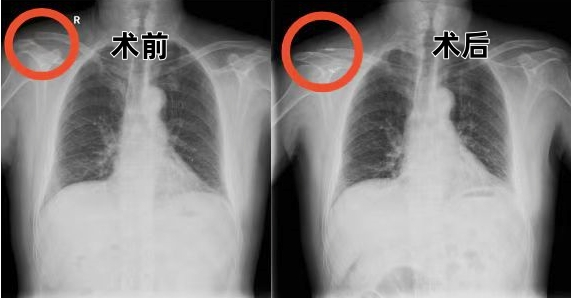

丁先生的病情到底是什么情况呢?骨科(关节、创伤,运医)中心主任甘煜东教授指着X线影像解释道:“患者的肩锁关节完全脱位,合并喙锁韧带断裂,属于RockwoodⅢ型损伤,这类损伤保守治疗容易遗留肩关节不稳、慢性疼痛等问题。传统手术创伤大、易残留肩部畸形,所以我们决定采用关节镜下袢钢板固定——就像用特制缆绳把脱位的关节精准锚定,这项技术对解剖重建的要求极高,但能最大限度保留肩关节功能。”

通过3个5毫米-10毫米的微小切口,在高清关节镜视野下,采用可调节带袢钛板模拟喙锁韧带生物力学轨迹,完成了解剖级精准重建。手术历时40分钟,出血仅5毫升。